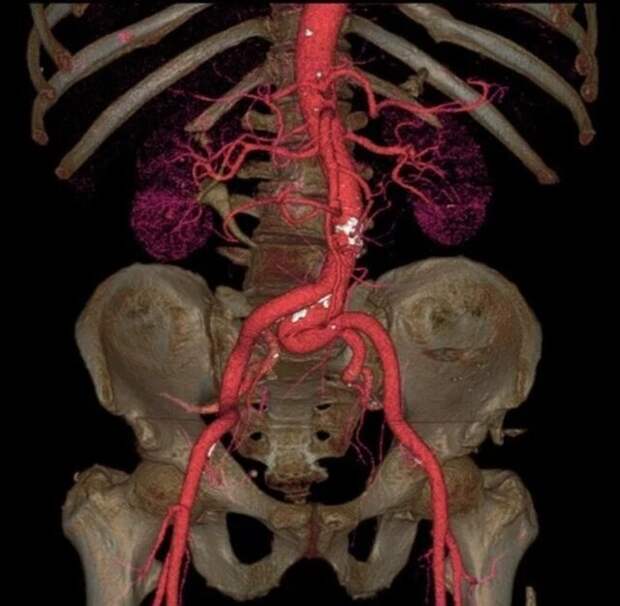

Рентген пациента, который прошел процедуру подтяжки лица золотыми нитями  Сканирование аорты, самой большой артерии нашего тела

Сканирование аорты, самой большой артерии нашего тела  Травма головы